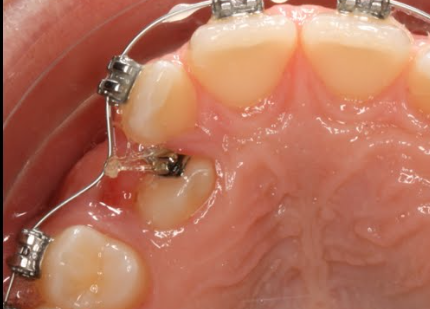

2. Colocación de aditamentos:

Una vez expuesto, se adhiere un pequeño aditamento (como un botón o una cadena) al diente, que servirá como punto de anclaje para la tracción.

3. Tracción ortodóntica:

Se utilizan aparatos ortodónticos, como brackets y alambres, para aplicar una fuerza gradual al diente, moviéndolo lentamente hacia su posición correcta en la arcada.

Tracción intramucosa (o submucosa):

El aditamento y el aparato de tracción se colocan debajo de la mucosa, de forma que el diente erupcione de manera cerrada.

Tracción extramucosa:

El diente se expone completamente y el aditamento se fija a él, permitiendo que el diente erupcione con mayor facilidad.